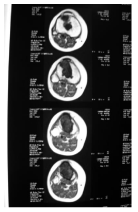

A 33 year - old female patient presented for right leg pain of a five week duration, exacerbated by weight bearing without disappearing at rest or at night. She estimates the pain as 6 over 10, relieved with non-steroidal anti - inflammatory agents. She is previously healthy without any history of trauma. There is mild edema, no redness, and mild increase of the pain upon palpation. There are no neurovascular abnormalities. Examination of the back, hip, and knee is normal. X-ray showed a large hypolucent spherical lesion in the proximal third of the tibia (Figure 1). MRI on T1 showed the lesion to be hypointense, and on T2 to be hyperintense (Figure 2,3). The lesion showed to be osteolytic, extending anteroposteriorly through the cortex at some levels, but it did not reach the articular surface, nor the surrounding soft tissues. Decision was taken to biopsy it. The pathology report showed lamellated cysts and scattered scoleces. Albendazole 400 mg was given orally twice per day for 2 months. Extensive curettage was done through excision of bone layers with a burr, then phenolization and grafting of cancellous bone chips inside the cavity. The patient was free clinically and radiologically of the disease for two years, then in the third year, multilocular cysts reappeared on x-ray (Figure 4), with possible extension to the articular surface. A decision of total knee arthroplasty was taken after wide resection of the diseased segment (Figure 5). Negative margins were obtained. The patient post operatively was rehabilitated; pain subsided with no radiological signs of recurrence. She was given albendazole 400 mg orally twice per day for 3 months.

Figure 3: Transverse T1 cuts, showing the anteroposterior involvement of the tibia. No soft tissue invasion.